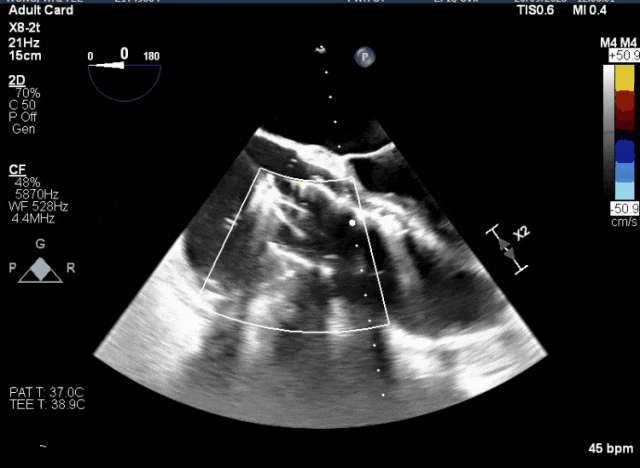

術中TEE觀察夾持件的位置

術后DSA

術后超聲評估瓣膜穩(wěn)定性良好,無瓣周漏